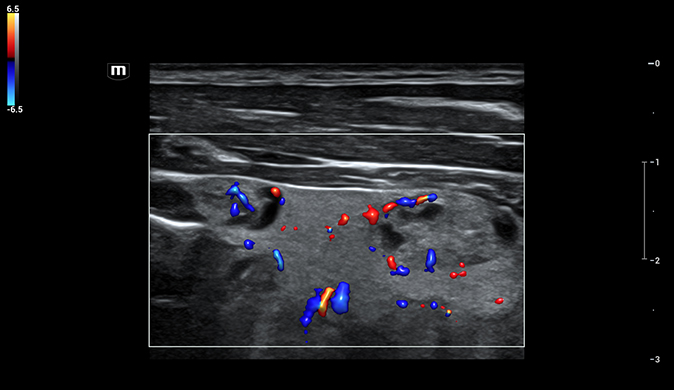

Das Resona I8 weist vielfältige klinische Lösungen auf, die speziell für den jeweiligen Anwendungsbereich entwickelt wurden. Die Technologie baut auf einem tiefgreifenden Verständnis verschiedener klinischer Szenarien auf und bietet eine umfassende Serie fortschrittlicher Diagnoseinstrumente, beispiellose Intelligenz und präzise Analysen zur Verbesserung von Diagnosesicherheit, Qualitätskontrolle und Scaneffizienz.